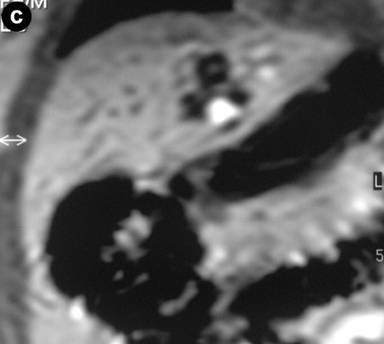

A 27-year-old female underwent a cholecystectomy for lithiasis. The patient was successively evaluated for diffuse and recurrent abdominal pain; no alcohol and/or smoking habits were reported. Laboratory measurements of total bilirubin and pancreatic amylases were unremarkable. Abdominal ultrasound was carried out which showed multiple hepatic and pancreatic cystic lesions; a dynamic enhanced CT scan confirmed the presence of multiple liver and pancreatic cystic lesions, but, in particular, the differentiation between simple hepatic cysts and cystic ectasia of the biliary ducts suggestive of Caroli’s disease was not reached. Therefore, MRI was requested to characterize the liver lesions and it was performed acquiring T1- and T2-weighted sequences integrated with T2-hydrographic images to specifically evaluate the biliary tract in axial and coronal views. MR cholangiography after intravenous administration of mangafodipir trisodium (Teslascan®, Nycomed, Amersham, Oslo, Norway), was also performed using T1-weighted sequences. Turbo spin echo T2-weighted images in axial and coronal views showed multiple hyperintense focal lesions in the left lobe of the liver, typical of cystic lesions, as well as multiple pancreatic cysts of the tail and saccular ectasia of the main biliary duct (Figure 1). T2-hydrographic dedicated images confirmed these findings, but certain imaging signs for a differential diagnosis between simple hepatic cysts and biliary cysts were not identified (Figure 2). However, the enhanced mangafodipir trisodium T1-weighted MRI clearly showed that some of the liver cysts concentrated mangafodipir trisodium contrast medium, thus demonstrating that these enhanced cystic lesions were in communication with the biliary ducts providing imaging criteria consistent with a diagnosis of Caroli’s disease (Figure 3). A segmental hepatectomy specimen demonstrated dilated simil-cystic intrahepatic ducts of the IV segment corresponding to a diagnosis of Caroli’s disease.

Figure 3. Enhanced mangafodipir trisodium T1-weighted axial (a. and b.) and coronal (c. and d.) MR views show that some of the liver cysts of the left lobe concentrate mangafodipir trisodium contrast medium as well as the fact that the main biliary duct has saccular dilatation. |